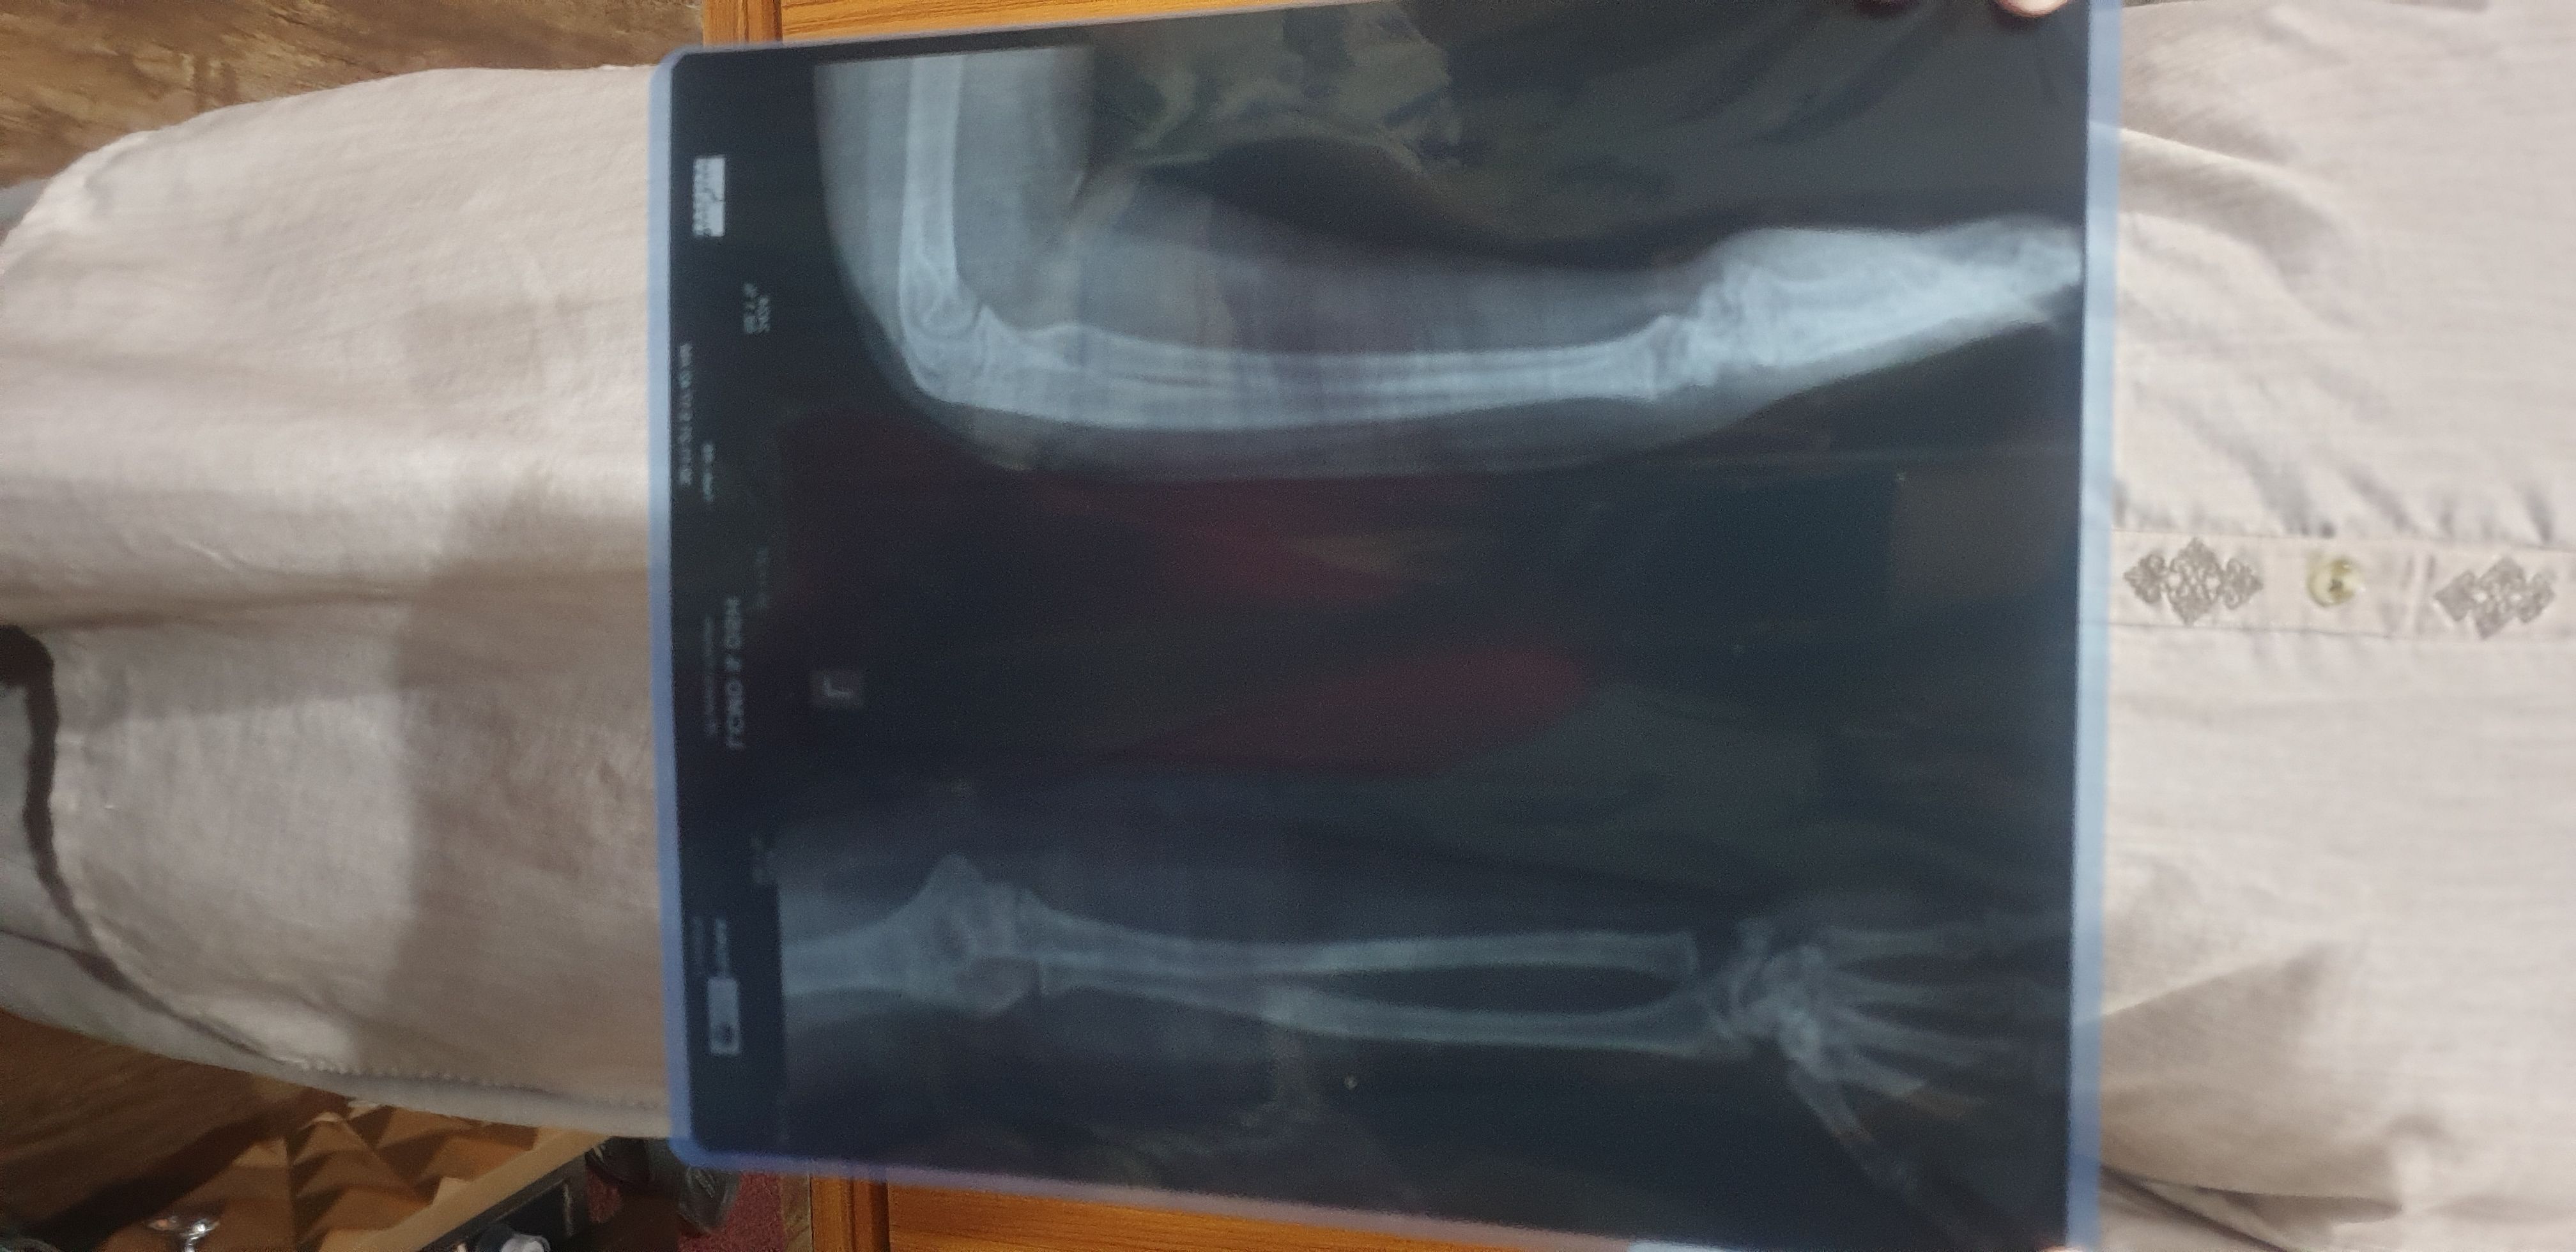

upload your medications plus x ray.

agar just dard ha tu dard ke lye painkillers ap konse le rahe ho?

xray

4 years ago

Member

Post Owner

ex ray